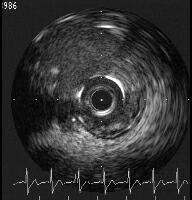

○○先生がおっしゃっていたS670のclosed cell、 落とし穴に運悪くはまり、研

究会で発表いたしましたのは私です。

DCA後の再狭窄病変に対し、S670 4x18mmをLMT-LADへ挿入いたしました。LCX

側を3mmのバルーンで拡張もステント部分のIndentationがとれず、IVUSを見

ましたところ2mm程度までしか拡がっていませんでした。jpg imageご参照ください。

○○先生が言われていましたS670のclosed cellに入ったためと思われます。

closed cellの部分をバルーン拡張にてふさぎながら、open cellへwireをrecrossさ

せ、拡張をいたしましたが、まん丸に拡がったclosed cellが邪魔をして、十分には

拡がりませんでした。今のところ発作はありませんが、LCXに再狭窄がきたらどう

しようかとおもっています。

どなたか、いいアイディアがありましたら、ご教示ください。